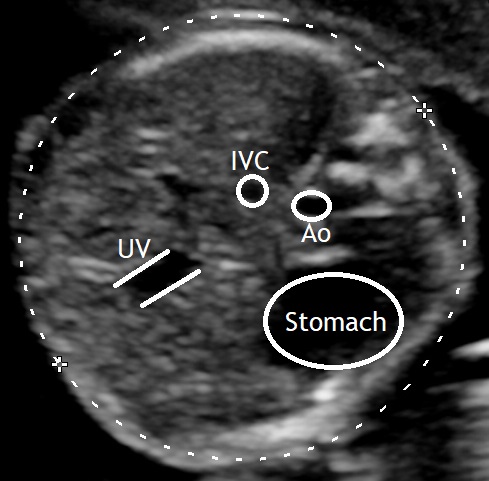

Campbell and Wilkin first described the acquisition of a section orthogonal to the long axis of the fetal body and across the upper abdomen; this was recognized by the typical appearance of the umbilical vein. In cases where the umbilical vein could not be visualized, the fetal stomach was the next most suitable reference point to be used. Then they would take a photograph of the ultrasound image and print it in life size to make their measurements. (Campbell and Wilkin, 1975).

In our days ultrasound machines provide images of much higher quality and measurements can be performed during the examination. However, the defined plane remains the same, as it is easily reproducible. Certainly using today’s technology, a few other anatomical landmarks can also be noted on the same plane.